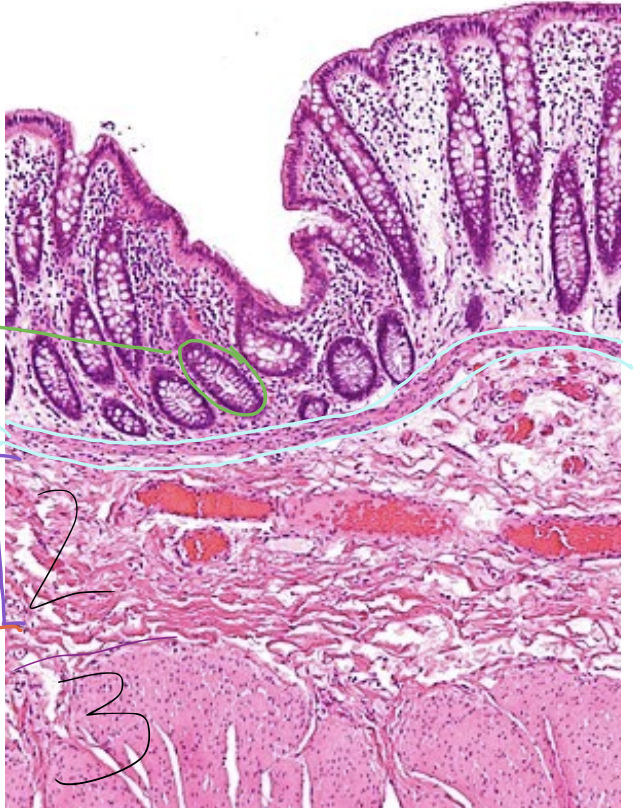

green circle

gland

blue lining

lamina muscularis

2

tunica submucosa

3

tunica muscularis